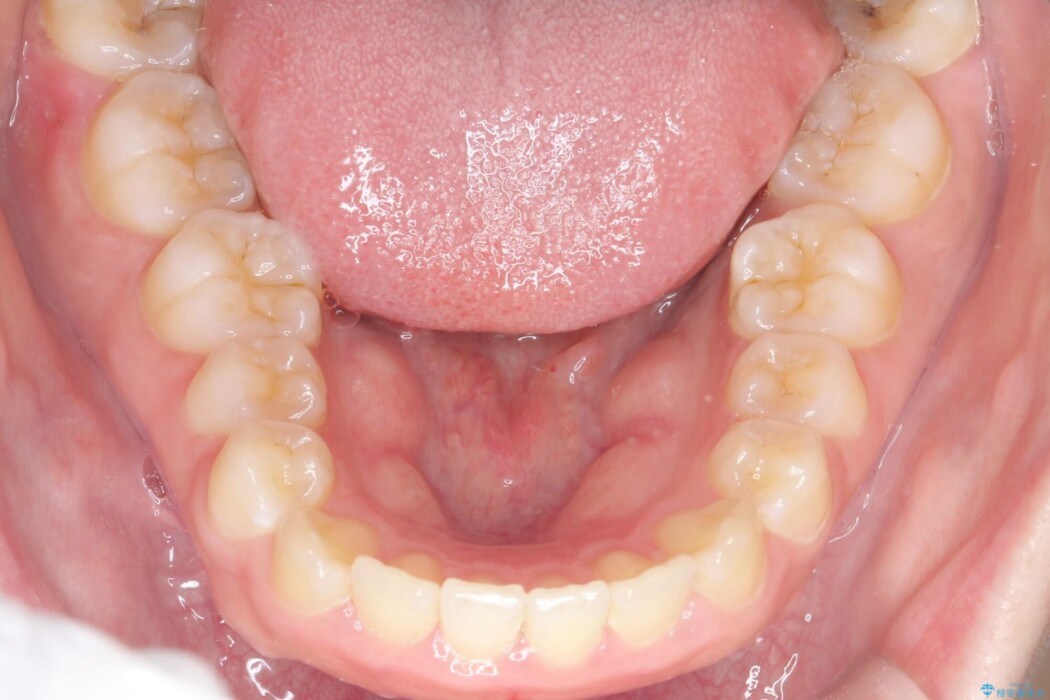

治療後について

抜歯で得たスペースを活用し、大きく傾いた前歯の角度を修正しながら、ゆっくりと後方へ移動させていきました。

抜歯スペースが閉じるにつれて、唇側の圧迫感が解消され、口元のボリュームが自然に抑えられていきました。

治療後は、口元の突出感が解消され、鼻先から顎先を結ぶ「Eライン」が劇的に変化し「自信を持って笑えるようになった」と大変喜んでいただけました。